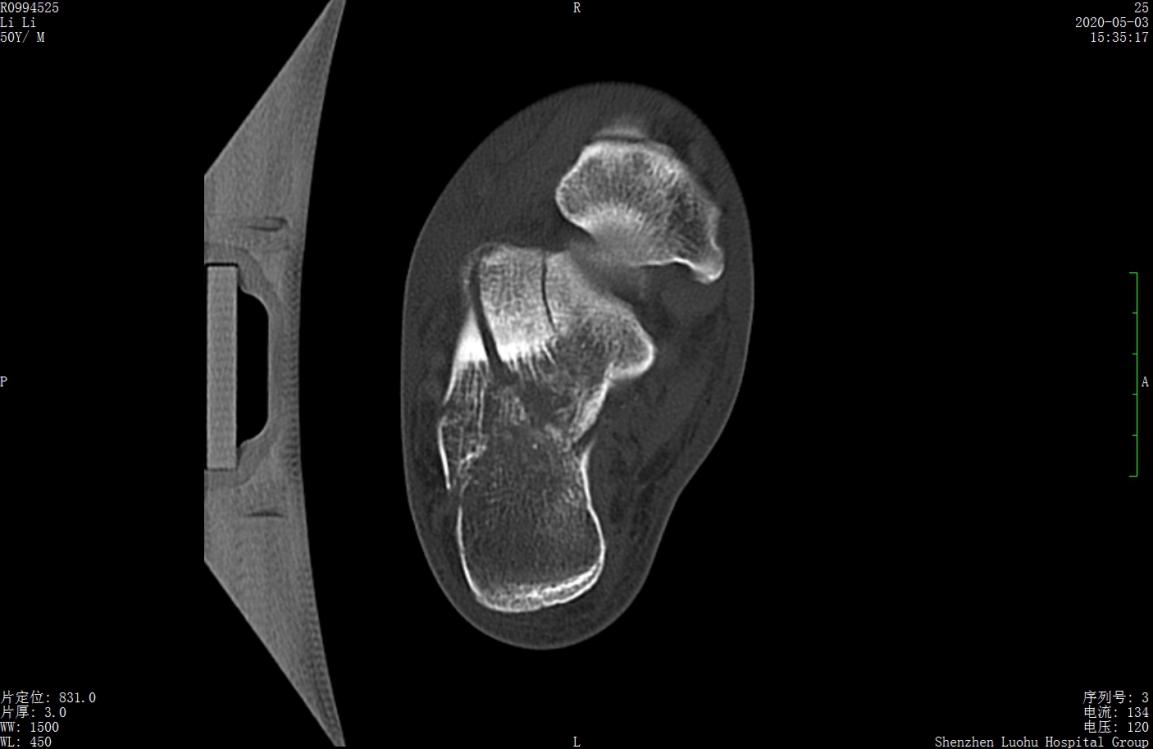

术前CT示跟骨严重粉碎骨折,移位明显